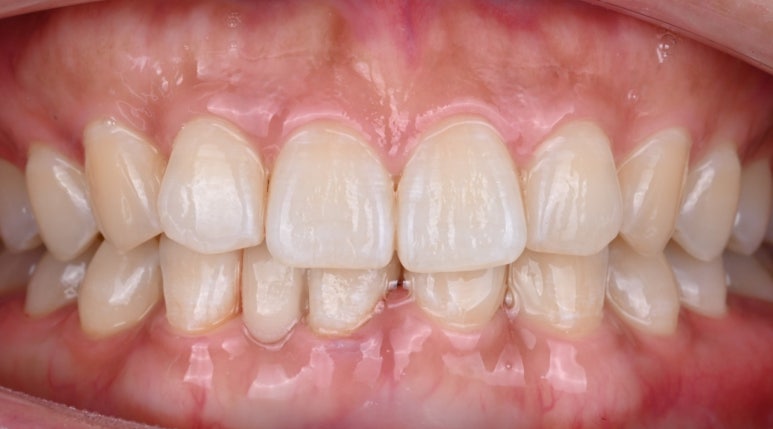

26.04.02 치료 후 모습

치료가 끝난 후,

환자분께서는 거울을 보며

한참 동안 미소를 지으셨습니다.

평생을 따라다니던 콤플렉스가

며칠 만에 해결되었기 때문입니다.

26.04.02 치료 후